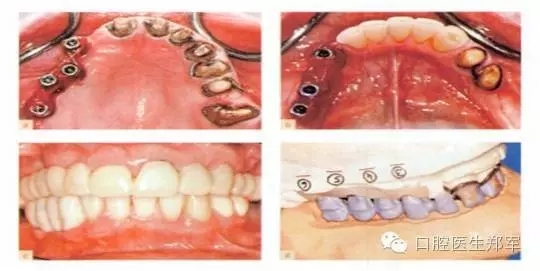

圖3下頜的治療選擇。a到d 固定“All on Four”修復和遠中傾斜植入。(圖片由Dr. B Marshak提供)。e 和f 由四個種植體支撐的下頜覆蓋義齒。 |

圖4 種植支持的覆蓋義齒或4個傾斜種植體支持的固定種植體支持式的修復。“All on Four”已經(jīng)廣泛的傳播,懷疑者等待更可靠的證據(jù)結果。臨床圖像由Dr. B Marshak提供。 |